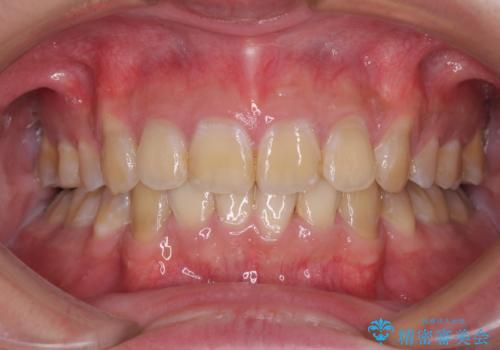

前歯のデコボコを治したい インビザラインによる矯正治療

担当医 藤巻太一朗